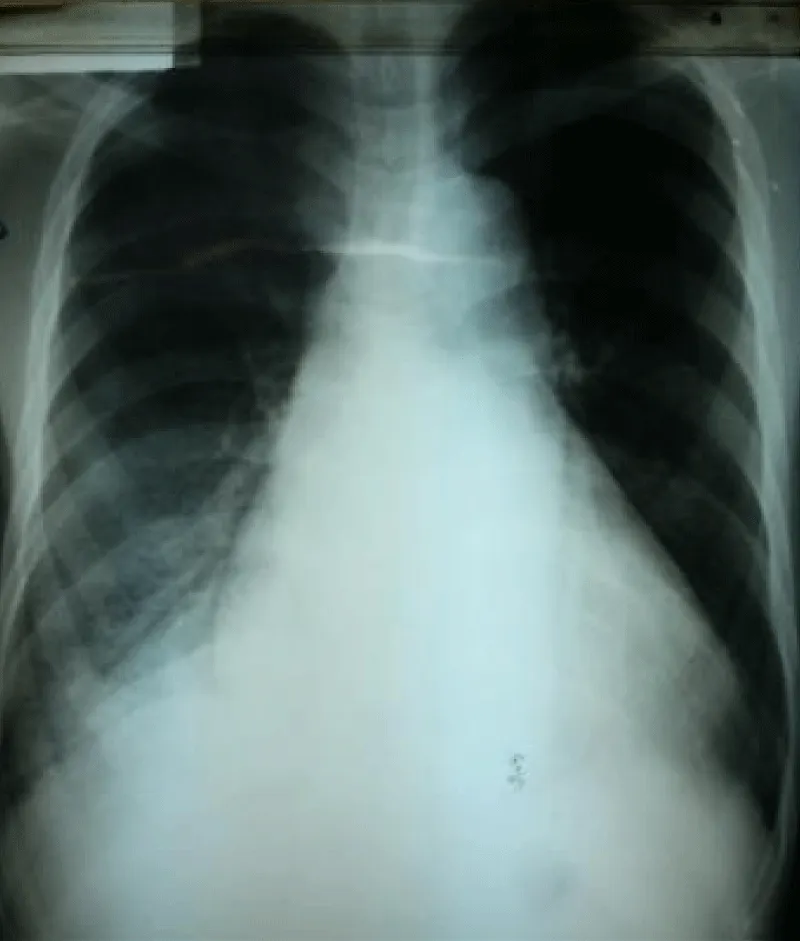

Laboratory examination reported a hemoglobin level of 12.2 g/dl with normal platelets and white blood cells count; Kidney function test and blood electrolytes were normal; the cycle of serum troponin and creatinine-phosphokinase levels were normal; HIV retroviral serology was negative. Chest x-ray reported a cardiomegaly (cardiothoracic index of 0.6) with pulmonary edema and an enlarged upper right arch of the mediastinum (Figure 1). A transthoracic electrocardiogram recorded regular sinus tachycardia (110 cycles per minute), left anterior hemiblock and poor progression of R waves in the anterior leads (Figure 2).

Figure 1: Frontal chest x-ray showing global cardiomegaly with signs of cardiac lung and enlargement of the upper mediastinum with overhang of the right upper arch.